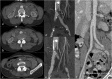

Objectives: To demonstrate the various presentations of acute aortic pathology and to present diagnostic and therapeutic approaches.

Methods: Diagnostic imaging is the key to the reliable diagnosis of acute aortic pathology with multi-slice computed tomography angiography (CTA) as the fastest and most robust modality. Endovascular aortic repair (EVAR) with stent grafts and open surgical repair are therapeutic approaches for aortic pathology.

Results: CTA is reliable in diagnosing and grading aortic trauma, measuring aortic diameter in aortic aneurysms and detecting vascular wall pathology in acute aortic syndrome and aortic inflammation. CTA enables planning the optimal therapeutic approach. Stent graft implantation and/or an open surgical approach can address vascular wall pathology and exclude aortic aneurysms.

Conclusion: Aortic emergencies have to be detected quickly. CTA is the imaging method of choice and helps to decide whether elective, urgent or emergent treatment is necessary with EVAR and open surgical repair as the main treatment approaches.

Teaching points: • To present aortic pathology caused by trauma • To present acute aortic syndrome (aortic dissection, intramural haematoma and penetrating ulcers) • To present symptomatic and ruptured aortic aneurysm • To present infection (mycotic aneurysms/aorto-duodenal fistulae) or iatrogenic injury of the aorta • To understand different presentations for treatment planning (EVAR and open surgery).